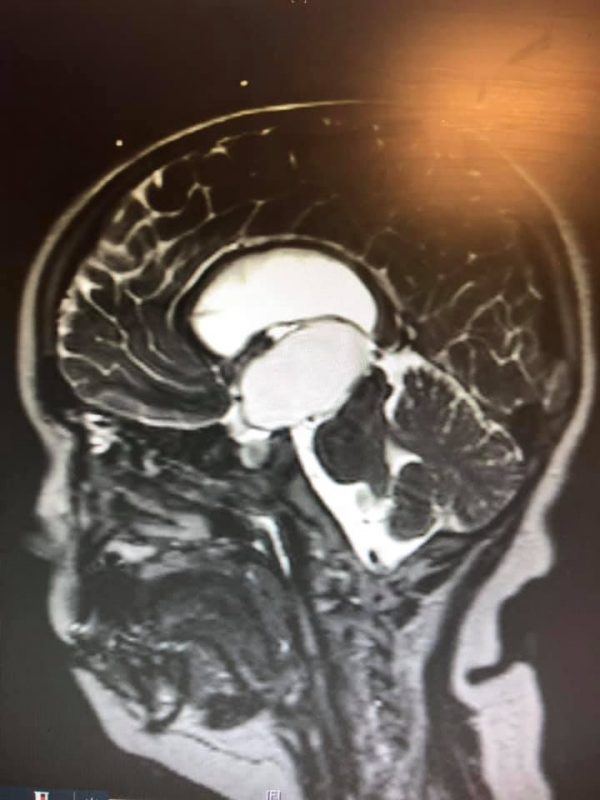

It was then that doctors diagnosed Danny with a brain tumor measuring five centimeters.

The tumor had caused a buildup of pressure in his brain, which was pressed against his skull as a result. This meant that he needed surgery to relieve the pressure and drain fluid from his brain.